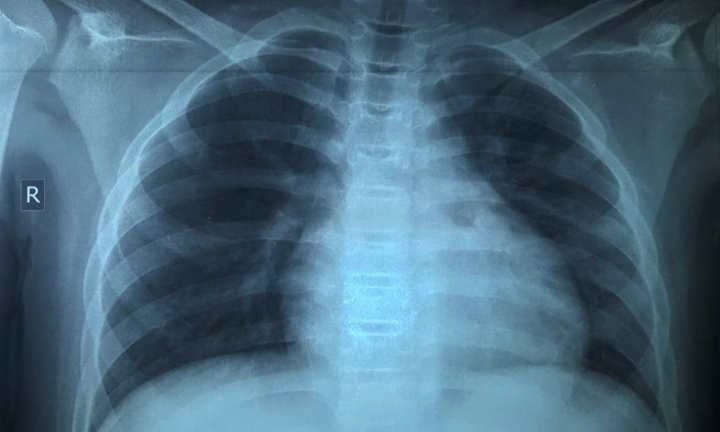

Bé trai 13 tuổi sau mắc COVID-19 đã bị tổn thương phổi nặng dù trước đó hoàn toàn khỏe mạnh, không có bệnh nền.